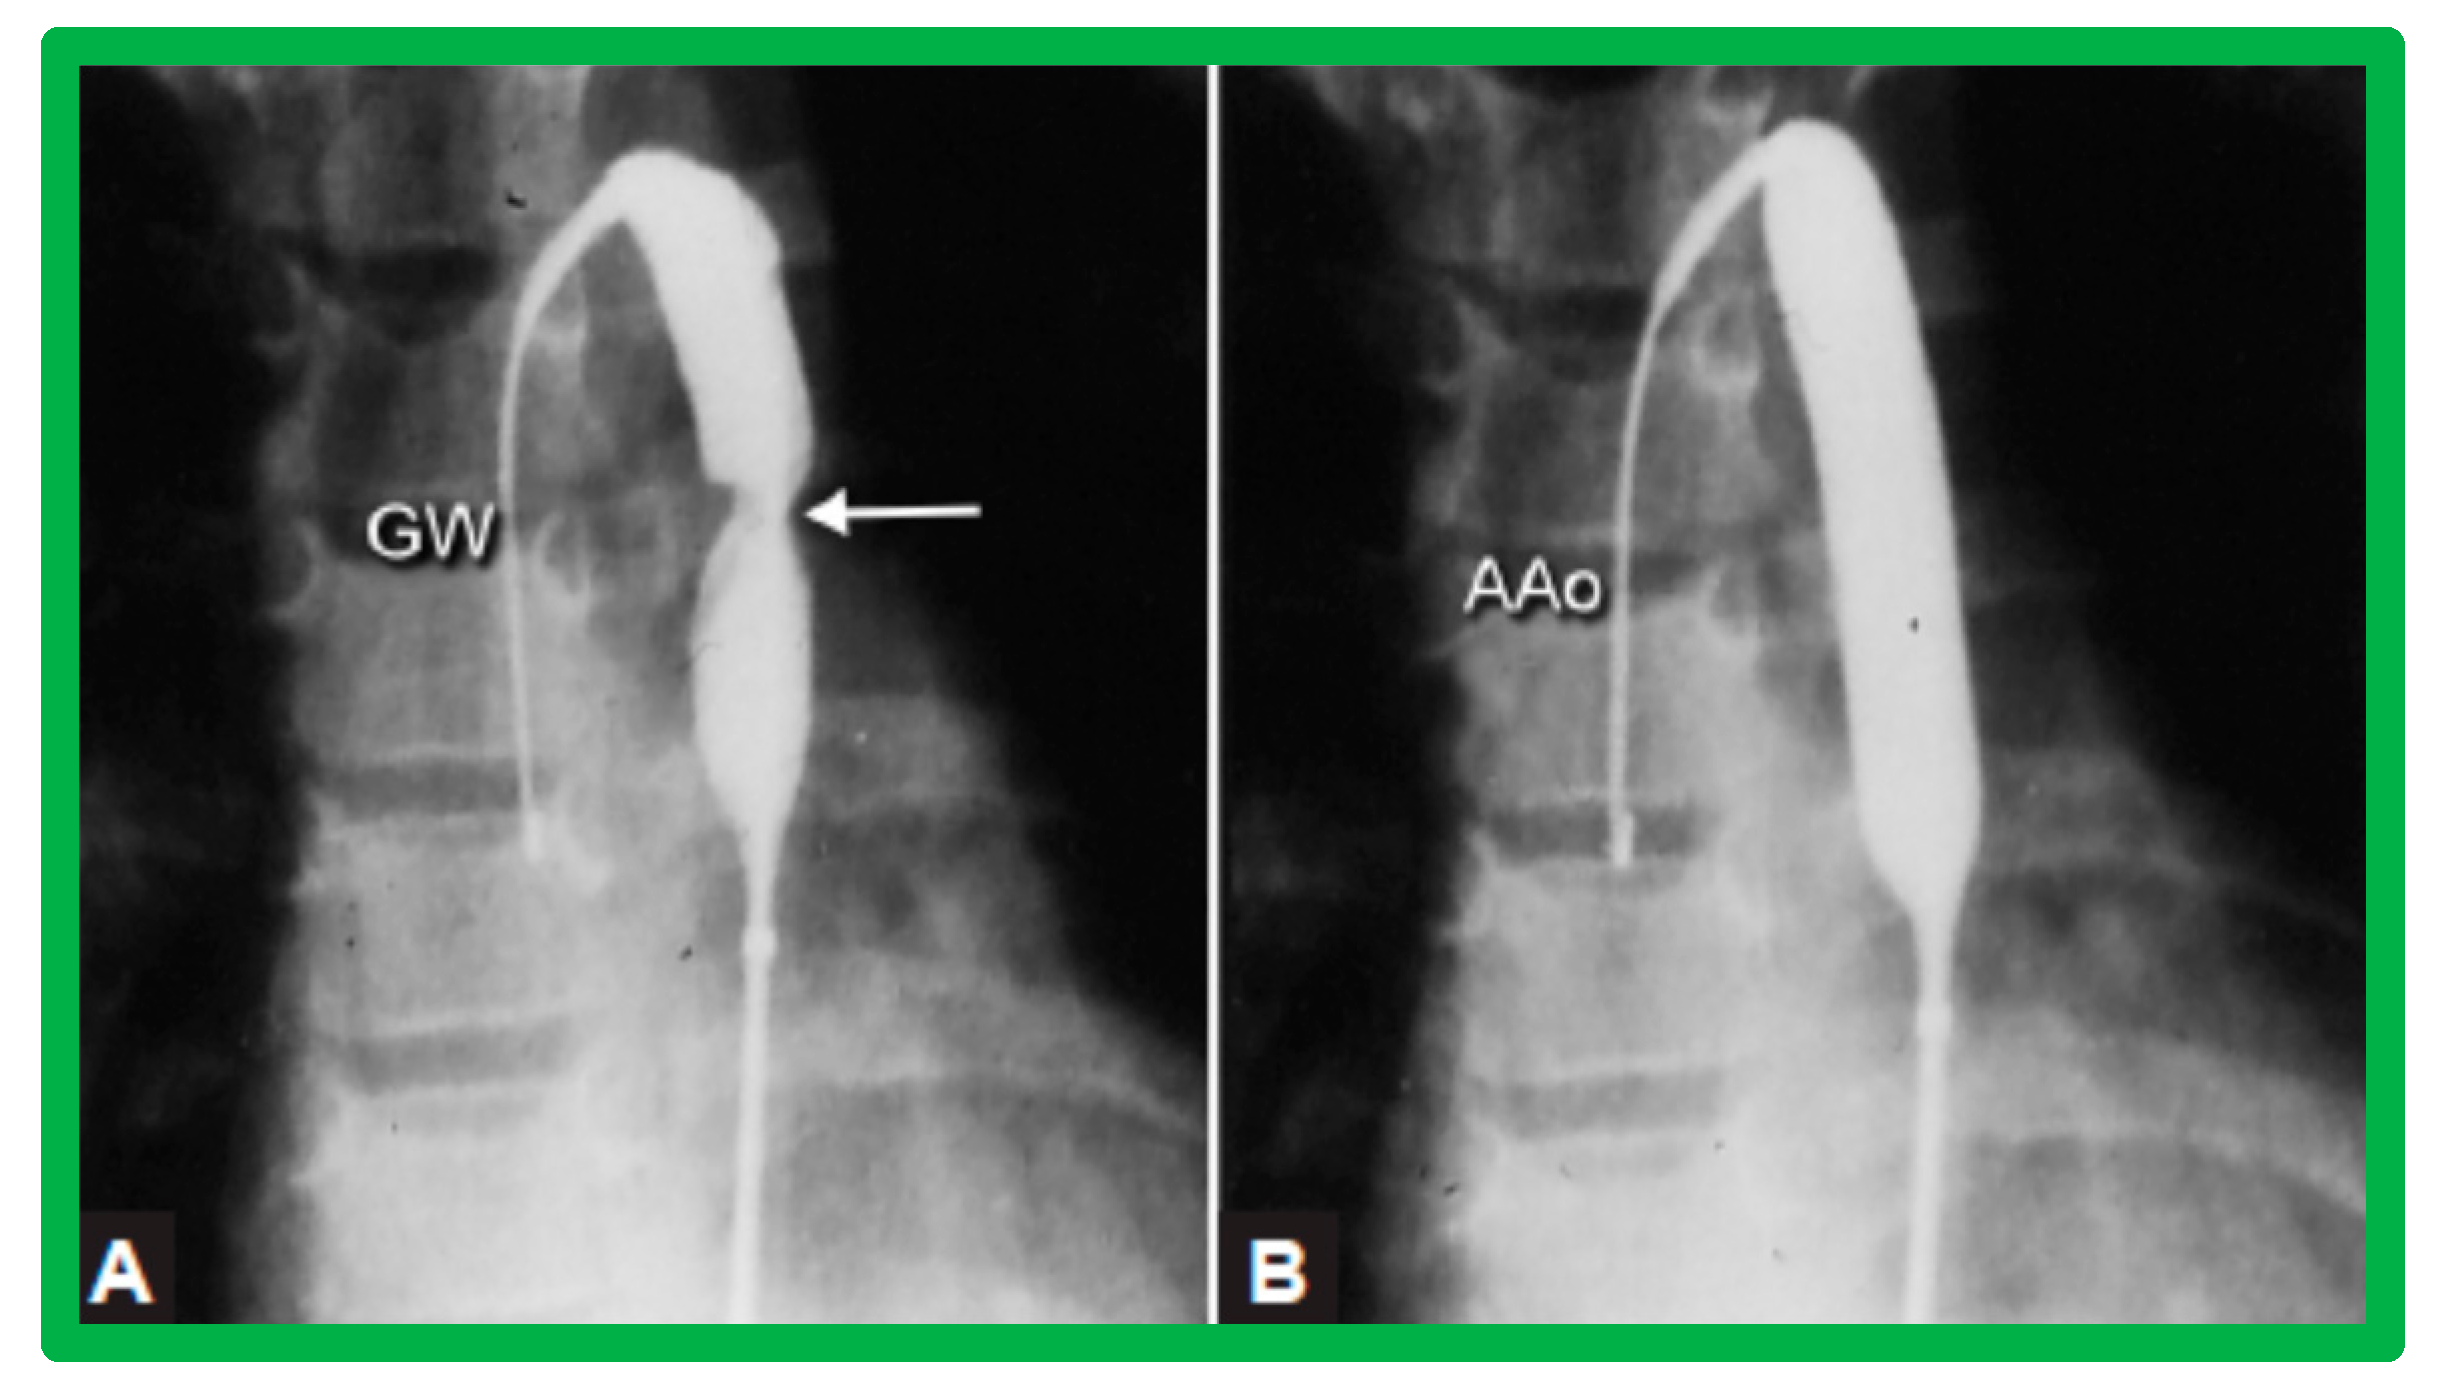

3.3. Aortic Coarctation, Native

3.4. Aortic Coarctation, Postsurgical